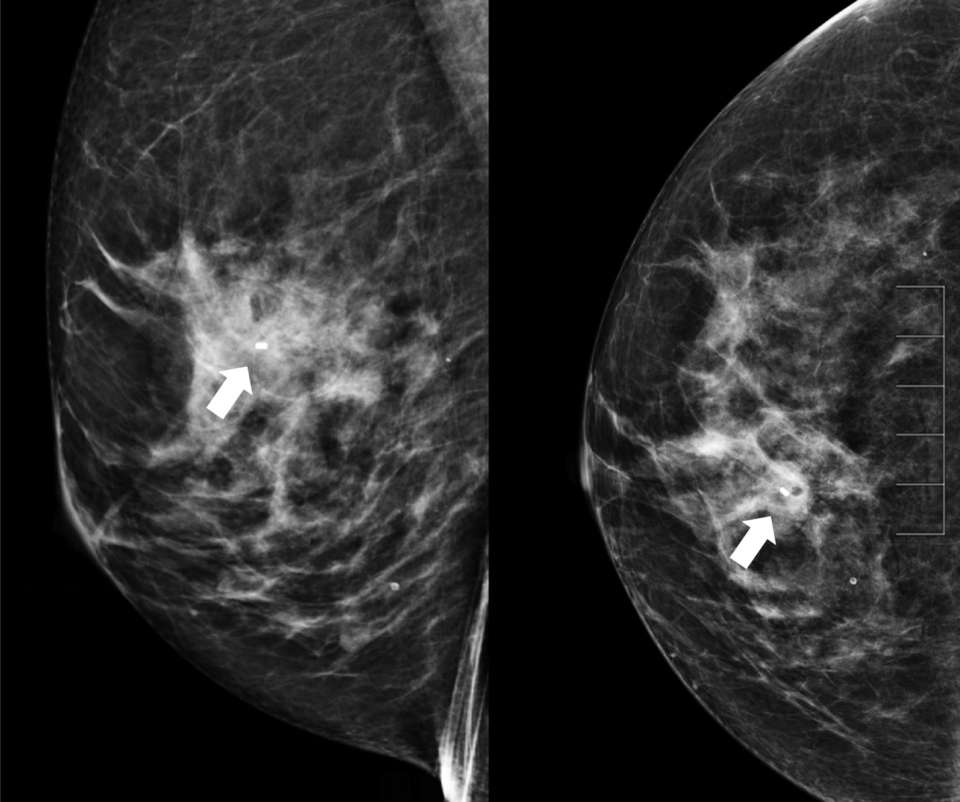

- Technologist takes 2D or 3D mammograms in CC and ML views (Figure 7).

- Radiologist evaluates for adequate biopsy marker placement.

Figure 7. Post-procedure ML (left) and CC (right) images demonstrate good biopsy marker placement (arrow).